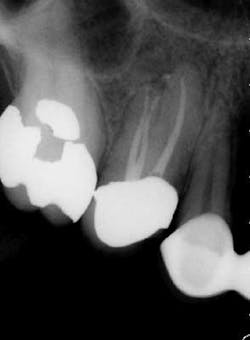

The success of endodontic treatment is directly related to the clinician’s ability to remove maximum numbers of bacteria from the root canal system. (1,2) If we can agree that all root canal treatment is associated with a certain degree of skill and precision in spite of perceived ease of treatment, I think it is fair to say there are no easy root canals. Some teeth are more difficult than others due to access limitations or anatomy, but the problem that faces all of us, in every tooth, is our inability to measure the absence of bacteria within the root canal and the potential for microanatomy to exist at any level of the root—whether it is a five-canal molar or a single-rooted anterior. It is impossible to determine the exact terminus of the root canal system, and there is no uniform agreement about where the root canal system ends. (3,4) The use of an apex locator can aid in this determination, but there is often disagreement between radiographic information and an apex locator, even in single-rooted anterior teeth, because the canal terminus can be at the radiographic apex or as much as 3 mm from it. (5) All instrumentation techniques leave a certain amount of the canal wall untouched, and we are not able to sterilize the root canal system. (6,7) The apical portion of any tooth may have dentinal tubules that can harbor bacteria, and the concept of a single uniform canal opening at the apex is anything but accurate. (8,9) Many teeth will have multiple portals of exit that may or may not be present in the apical third of the root. (Figure 1) As a result, the clinician must assume the apical canal anatomy in every tooth is highly variable in size, shape, and number (10,11,12) and there are no “easy ones.”

maxillary central incisor with a necrotic pulp. A prominent lateral canal can be seen,

but there is no way to know if multiple microscopic branches are present at any level

of the root canal system.